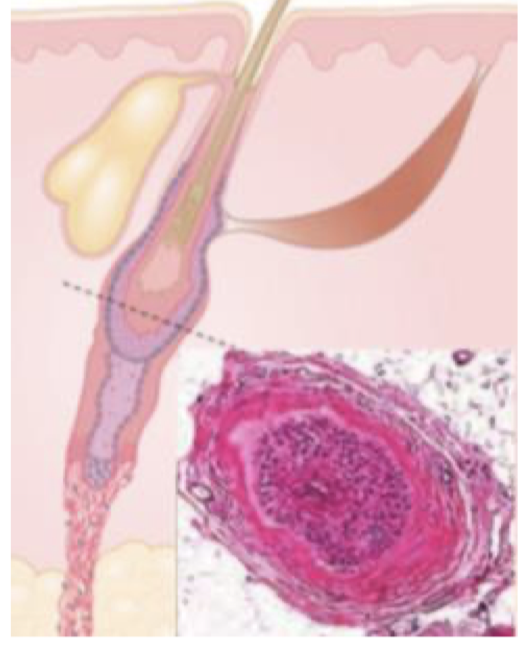

A

Terminal ANAGEN with glycogenated ORS & keratinized IRS